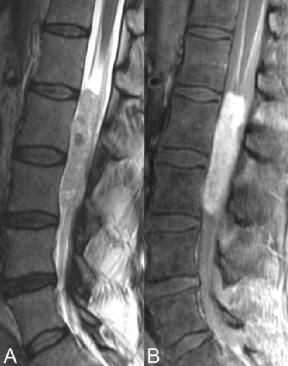

与其他以髓内肿瘤为主的肿瘤(星形细胞瘤)不同,室管膜瘤常累及腰椎,是圆锥、马尾和终丝最常见的肿瘤。与星形细胞瘤不同,它们的中枢、髓内

位置反映了它们在室管膜细胞中的起源,室管膜细胞排列在整个脊髓的含脑脊液中央管中。图51.4 A、B中的病变从L1延伸至L3,几乎充满椎管并导致神经根移位。其与脊髓的等信号至轻微高信号被低信号的小病灶打断,可能代表出血成分或高细胞区。

▲ 图51.4

钙化在T2WI上可能有类似的表现,尽管这在脊髓室管膜瘤中比在脑室管膜瘤中要少见得多。此外,增强T1WI缺乏相应的低信号(B),所以钙化不太可能。T2WI上该病变的信号实际上略大于典型细胞型室管膜瘤的信号。事实上,在下脊髓内,尤其是在终丝区(90%),粘液乳头状亚型更为常见,图51.4中粘液乳头状室管膜瘤内的大量粘液分泌物导致上出现T2WI高信号。同样,在T1WI上,粘液型病变的信号高于等信号(对脊髓)细胞型室管膜瘤。粘液型病变也往往比细胞型病变更大,出血更频繁。粘液亚型和细胞亚型均呈强烈但不均匀的增强,这种增强可能勾勒出肿瘤的囊性区域,在其他序列上,这些囊性区域通常与脑脊液呈等信号。在该特定患者病例中,图51.4 B中圆锥周围的额外增强被认为可能代表转移性扩散。手术时证实了这一点,同时证实了附近神经根的受累和附着。除了上述特征之外,室管膜瘤与星形细胞瘤的区别还在于其出血倾向、含有低信号高细胞区以及边界划分更为精确。